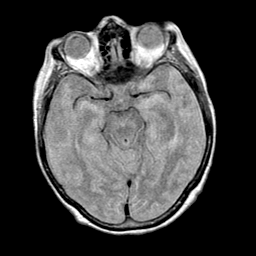

Pick's Disease, MR Study mr-pd -- Slice #8

[Home][Help][Clinical] Slice 8